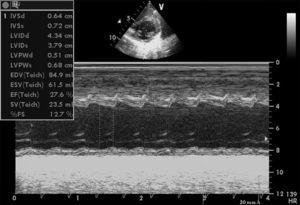

Niña de 5 años sin antecedentes de interés salvo cansancio a moderados esfuerzos un año antes, derivada a nuestro centro tras objetivar taquicardia (150 lat./min). El electrocardiograma objetivó taquicardia a 150 lat./min, con intervalo QRS estrecho y morfología de la onda P anómala con eje en el plano frontal de 120° (P negativa en DI) (fig. 1). La radiografía de tórax reveló la presencia de cardiomegalia y signos de edema pulmonar. En el estudio ecocardiográfico inicial (fig. 2) se observó un diámetro de ventrículo izquierdo (VI) telediastólico (DTD) de 44 mm y telesistólico (DTS) de 37 mm con una fracción de acortamiento (FA) del 27,6 % con una insuficiencia mitral moderada. Se realizaron bajo monitorización maniobras vagales obteniéndose cambio a ritmo sinusal durante segundos. Se inició tratamiento con digoxina y diuréticos presentando una disminución de la frecuencia cardíaca. A las 48 h se suspende el tratamiento con digoxina, iniciándose amiodarona, revertiendo a ritmo sinusal. En el control ecocardiográfico a los 5 días de tratamiento persistía la dilatación del VI con una FA del 47 %. El registro Holter inicial (a los 7 días) muestra la presencia de taquiarritmia auricular autolimitada, sugestivo de un foco auricular ectópico izquierdo; siendo normales los posteriores. El tamaño del VI disminuyó progresivamente (DTD de 37 mm) con recuperación de la función sistólica (FA 73 %) a los 4 meses (fig. 3), suspendiéndose el tratamiento con amiodarona, sin presentar recurrencias tras 9 meses de seguimiento.

Figura 2. Ecocardiografía Doppler en modo M. Se observa un ventrículo izquierdo dilatado con un DTD de 44 mm y un DTS de 37 mm con una fracción de acortamiento del 27,6 %.